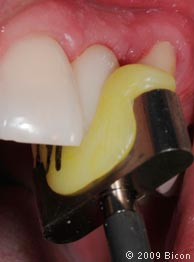

60. Правильное позиционирование коронки по длинной оси штифта абатмента и ложа имплантата происходит с помощью желтого посадочного шаблона из термопластмассы, изготовленного заранее. Шаблон закрепляют на прямом держателе.

61. Правильное позиционирование коронки по длинной оси штифта абатмента и ложа имплантата происходит с помощью желтого посадочного шаблона из термопластмассы, изготовленного заранее. Шаблон закрепляют на прямом держателе.